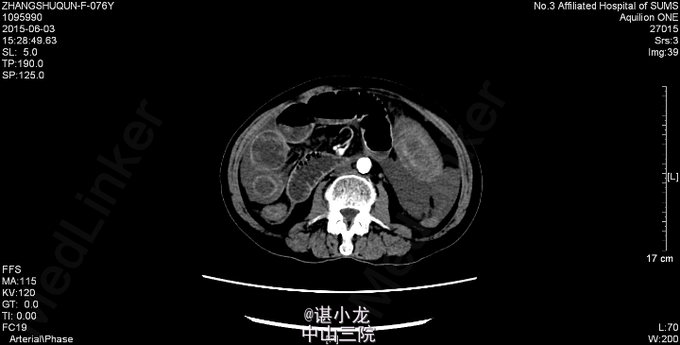

腹平坦,腹部未见曲张静脉、色素沉着,未见手术疤痕,未见胃型、肠型,腹肌软,全腹部压痛、反跳痛,未触及包块,腹部叩诊呈鼓音,肝脾肋下未触及,Murphy(-),肝浊音界叩诊不清,肝区、双肾区无叩痛,腹部移动性浊音(-),肠鸣音3-4次/分。直肠指检未扪及肿物,退指套无血染。 2015-6-3我院急诊腹部CT:空肠扭转,并小肠壁广泛水肿、增厚;腹盆腔中量积液。腹主动脉、双侧髂动脉、双肾动脉、脾动脉硬化。 血常规:白细胞总数16.490x10E9/L,中性粒细胞百分率0.877。凝血四项:凝血酶原时间>200.000sec,活化部分凝血酶时间>180.000sec。大便潜血试验阳性。肝功未见异常,生化示低钠131mmol/L,肌酐260umol/L。